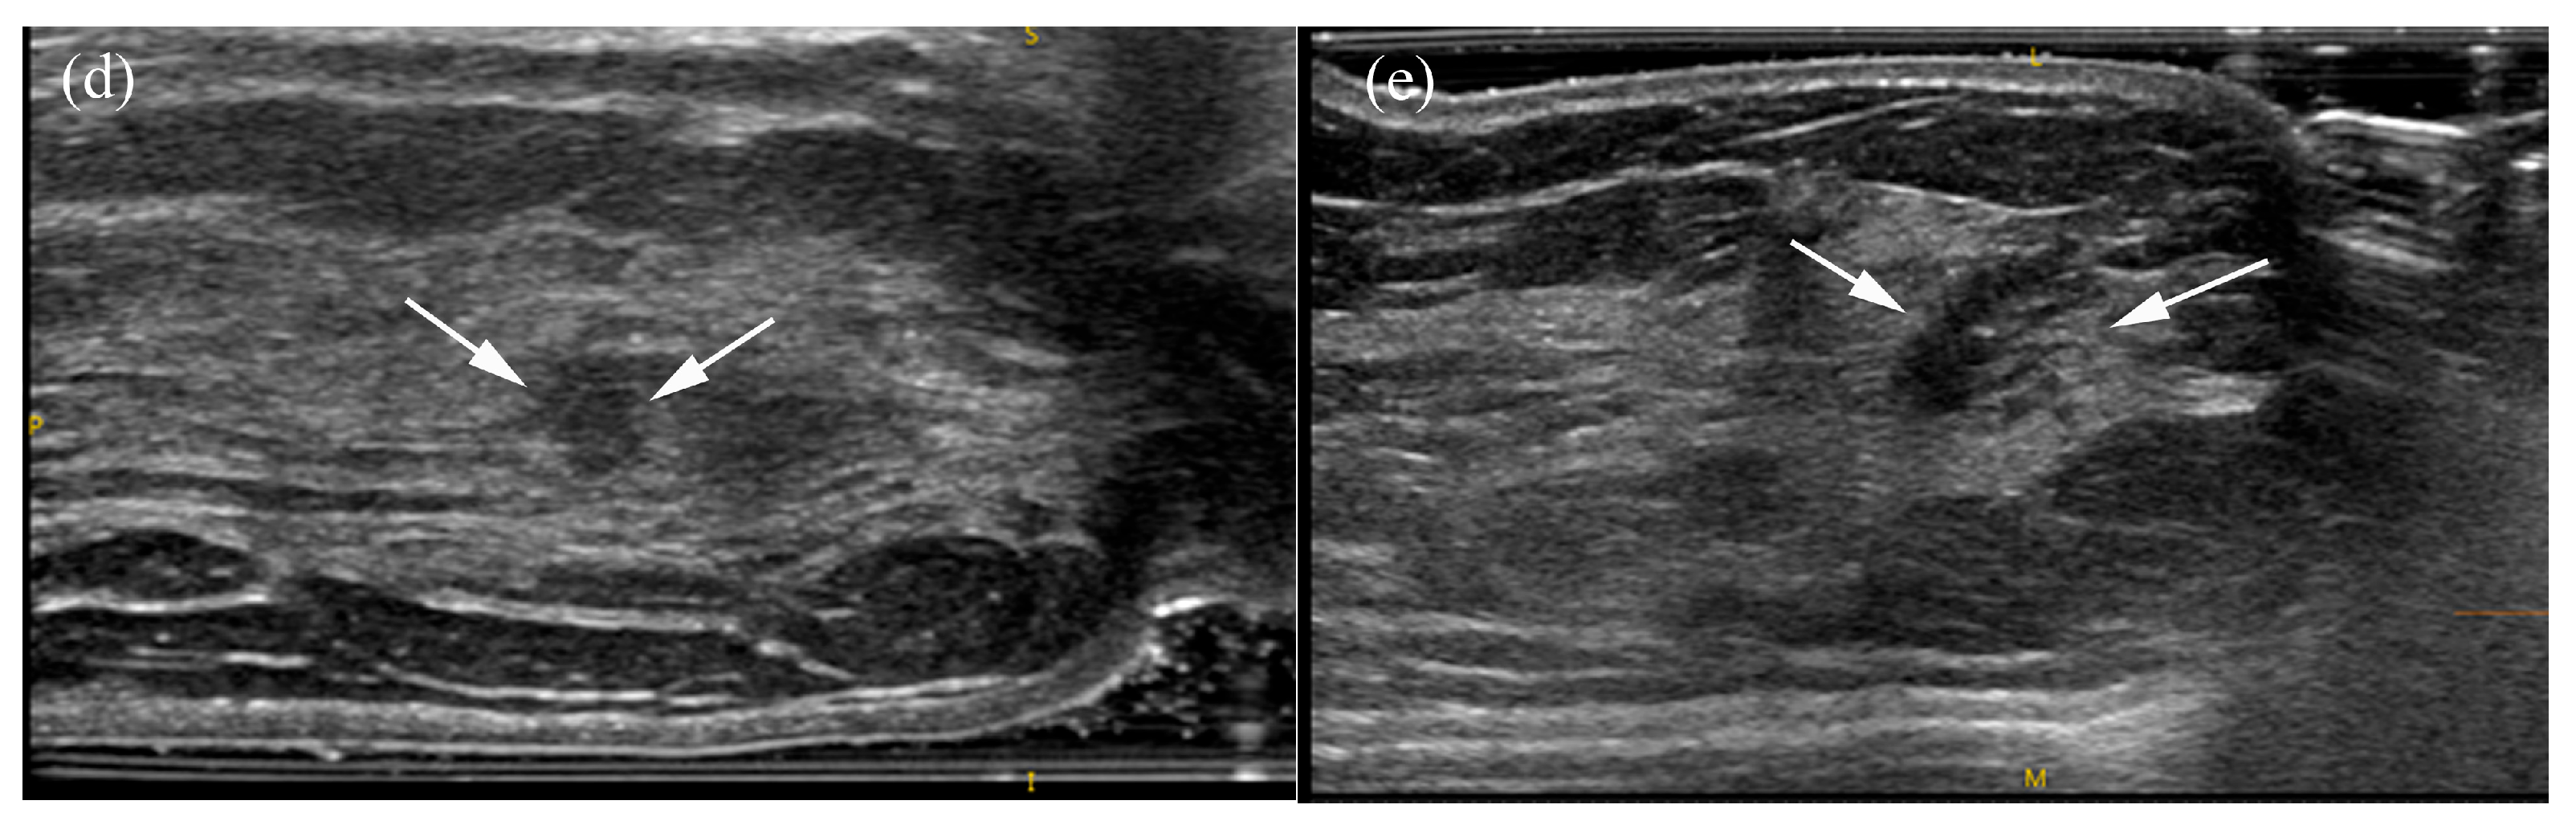

Figure 4. A 66-year-old female patient with screen-detected invasive lobular and ductal carcinoma: (a,b) The malignancy is not visualized on digital breast tomosynthesis (DBT). (c) Hand-held ultrasound reveals a spiculated, irregular, heterogeneous hypoechoic mass (arrows) in the left 12 o’clock area. (d,e) MammouS-N transverse images in craniocaudal (d) and mediolateral oblique (e) views demonstrate an indistinct, irregular, heterogeneous hypoechoic mass (arrows) in the central upper area of the left breast. S = superior, I = inferior, and M = medial.

Table 5 summarizes the factors influencing lesion visibility on DBT and MammouS-N images. Lesions that were better visualized on MammouS-N included masses obscured on DBT and non-calcified lesions (p ≤ 0.005) (Figure 4 and Figure 5). Reviewer 2’s assessment showed that larger lesions tended to be better visualized using DBT. No significant associations were observed between lesion visibility and factors such as patient age, mammographic density, lesion size on MammouS-N, echotexture, or lesion type (Figure 6).